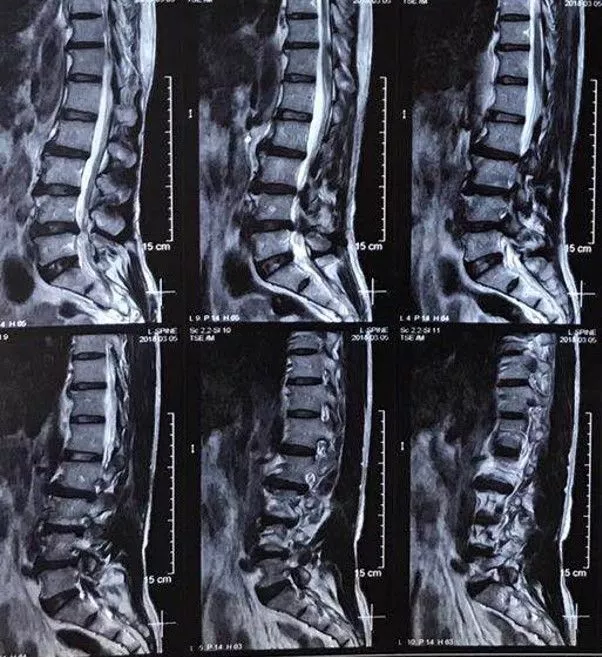

男性,59岁,半年前无诱因出现右半身麻木,伴右侧肢体乏力,右胸壁多汗,行走后右下肢抽痛明显,于当地医院就诊,查颈椎+胸椎+腰椎MRI示“颈髓脊髓空洞,腰4-5椎间盘突出”,对症治疗后症状无明显缓解。现为求进一步诊治,来西安交通大学第一附属医院,门诊以“脊髓空洞”收住入院。

影像学资料

3. 腰4-5椎间盘突出